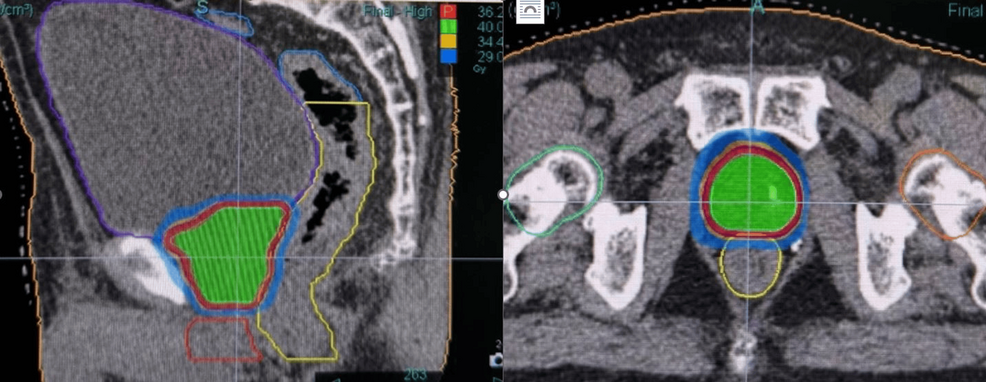

This retrospective study examines cancer control and health-related quality of life (HRQOL) outcomes in high-risk prostate cancer patients receiving robotic stereotactic body radiation therapy (SBRT) with Synchrony® real-time adaptive motion management.